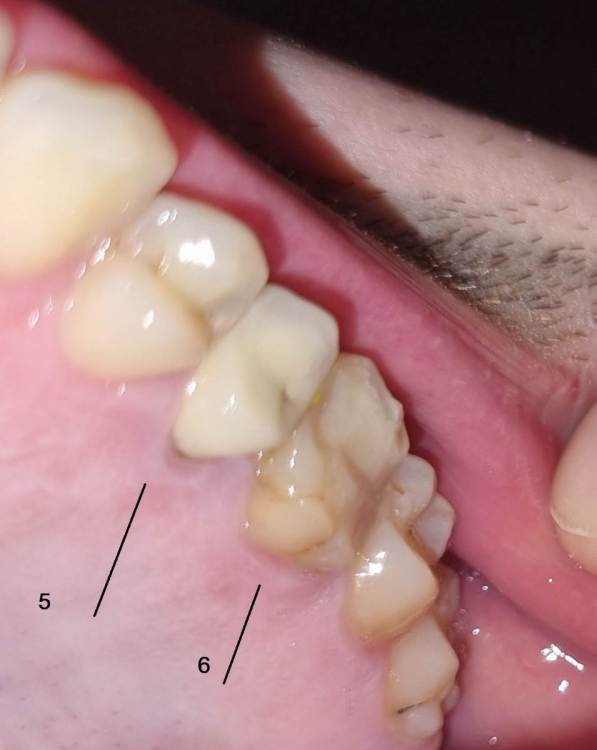

Chelovek2012 Опубликовано 17 апреля, 2023 Поделиться Опубликовано 17 апреля, 2023 (изменено) Всем добрый день. У меня вопрос. Верхняя левая 6-ка: Зуб давно был с запломбироваными каналами. Месяц назад их перепломбировали. Вкрутили в середину зуба какие-то как шурубчики для укрепления. И доктор говорит, что будет коронка Можно ли поборотся и спасти зуб, в который уже вкручены шурупчики для укрепления? 3 стенки зубы точно вижу на фото. Или нету смысла и он разлетится? Пломбировать уже нету смысла? Или технология пломбирования уже тут не подходит? 5 зуб возле него. Врачь говорит сразу сменить и эту коронку (ей 10 лет), так как между зубами есть нестыковка - темное место на рентгене между зубами Изменено 17 апреля, 2023 пользователем Chelovek2012 Ссылка на комментарий

Chelovek2012 Опубликовано 18 апреля, 2023 Автор Поделиться Опубликовано 18 апреля, 2023 (изменено) Спасибо. 3 Я просто думал, что в 2023 году уже есть технология сохранения зуба со стенками, чтобы не спиливать его и не ставить коронку. Зуб у меня новый не выростет больше никогда. Хотел поборотся за зуб. Скажите, а по фото/ренгтену можно ли определить, что коронка 5 зуба нуждается в замене? Изменено 18 апреля, 2023 пользователем Chelovek2012 Ссылка на комментарий

IvanK Опубликовано 20 апреля, 2023 Поделиться Опубликовано 20 апреля, 2023 20 часов назад, Chelovek2012 сказал: А это касается и других зубов, у которых есть только стенки? Нету технологии спасти зуб (во своих стенках) без коронки? покажите панорамный снимок (ОПТГ), тогда смогу сказать о других зубах судя по рг снимку есть все шансы получит кариес корня 5го зуба, что приведет к удалению зуба по поводу технологии спасения зубов - это только профилактика стоматологических заболеваний, а именно самостоятельная и профессиональная гигиена полости рта, своевременные осмотры и диагностические мероприятия у врача-стоматолога 1 Ссылка на комментарий